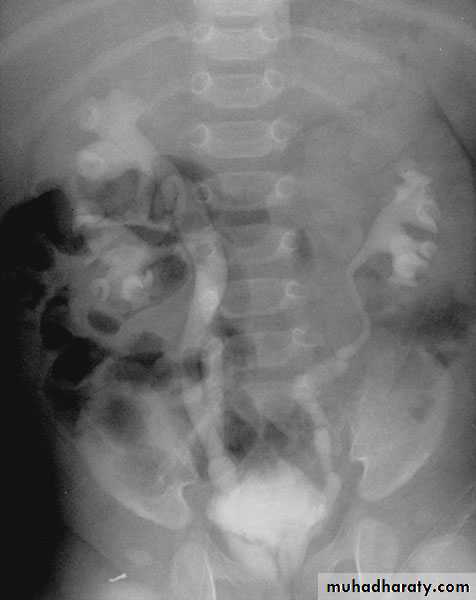

The right ureter pass behind the inferior vena cava

This might causes obstruction

Vascular abnormality

Incidence: about 1 in 1500Although it is congenital, most patients present at 3rd or 4th decade.

Diagnosis: IVU

Treatment:

surgical correction involves ureteral division, with relocation and ureteroureteral or ureteropelvic reanastomosis,

usually with excision or bypass of the retrocaval segment, which can

be aperistaltic